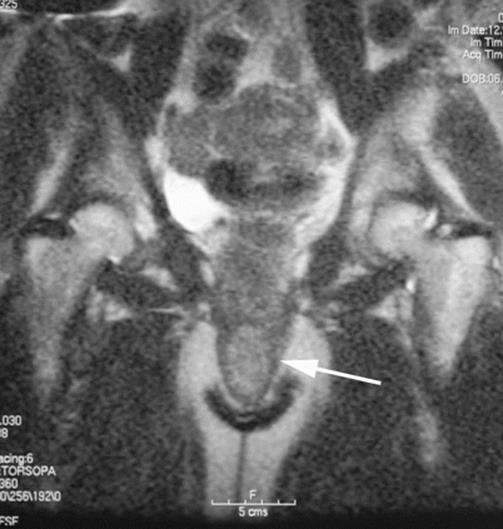

Fig. 8.2

Axial MRI showing a cystic lesion in the right labia. The cyst contains clear fluid (arrow)